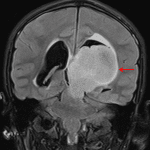

- T1 hypointense, T2 hyperintense, nonenhancing mass measuring 4.6 x 5.5 x 5.8 cm centered in the left thalamus with inferior extension into the left eccentric midbrain, lateral extension into the posterior limb of the left internal capsule, and superior extension into the left frontoparietal periventricular white matter

- Areas of internal restricted diffusion, particularly in the inferior and anterosuperior aspects of the mass

- Associated obstructive hydrocephalus at the level of the posterior third ventricle and cerebral aqueduct with subependymal edema and supratentorial sulcal effacement

Diffuse midline glioma